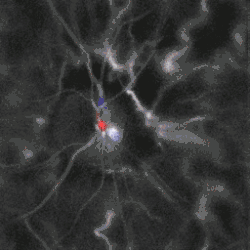

Blood flow in the retina and choroid in the optic disc region can be revealed non invasively by near-infrared laser Doppler imaging.[4] Laser Doppler imaging can enable mapping of the local arterial resistivity index, and the possibility to perform unambiguous identification of retinal arteries and veins on the basis of their systole-diastole variations, and reveal ocular hemodynamics in human eyes.[5] Furthermore, the Doppler spectrum asymmetry reveals the local direction of blood flow with respect to the optical axis. This directional information is overlaid on standard grayscale blood flow images to depict flow in the central artery and vein.[6]

Blood flow in the optic disc revealed by holographic laser Doppler imaging.[4]

Local direction of blood flow with respect to the optical axis revealed by the Doppler spectrum asymmetry in out-of-plane retinal vessels by holographic laser Doppler imaging.[6]